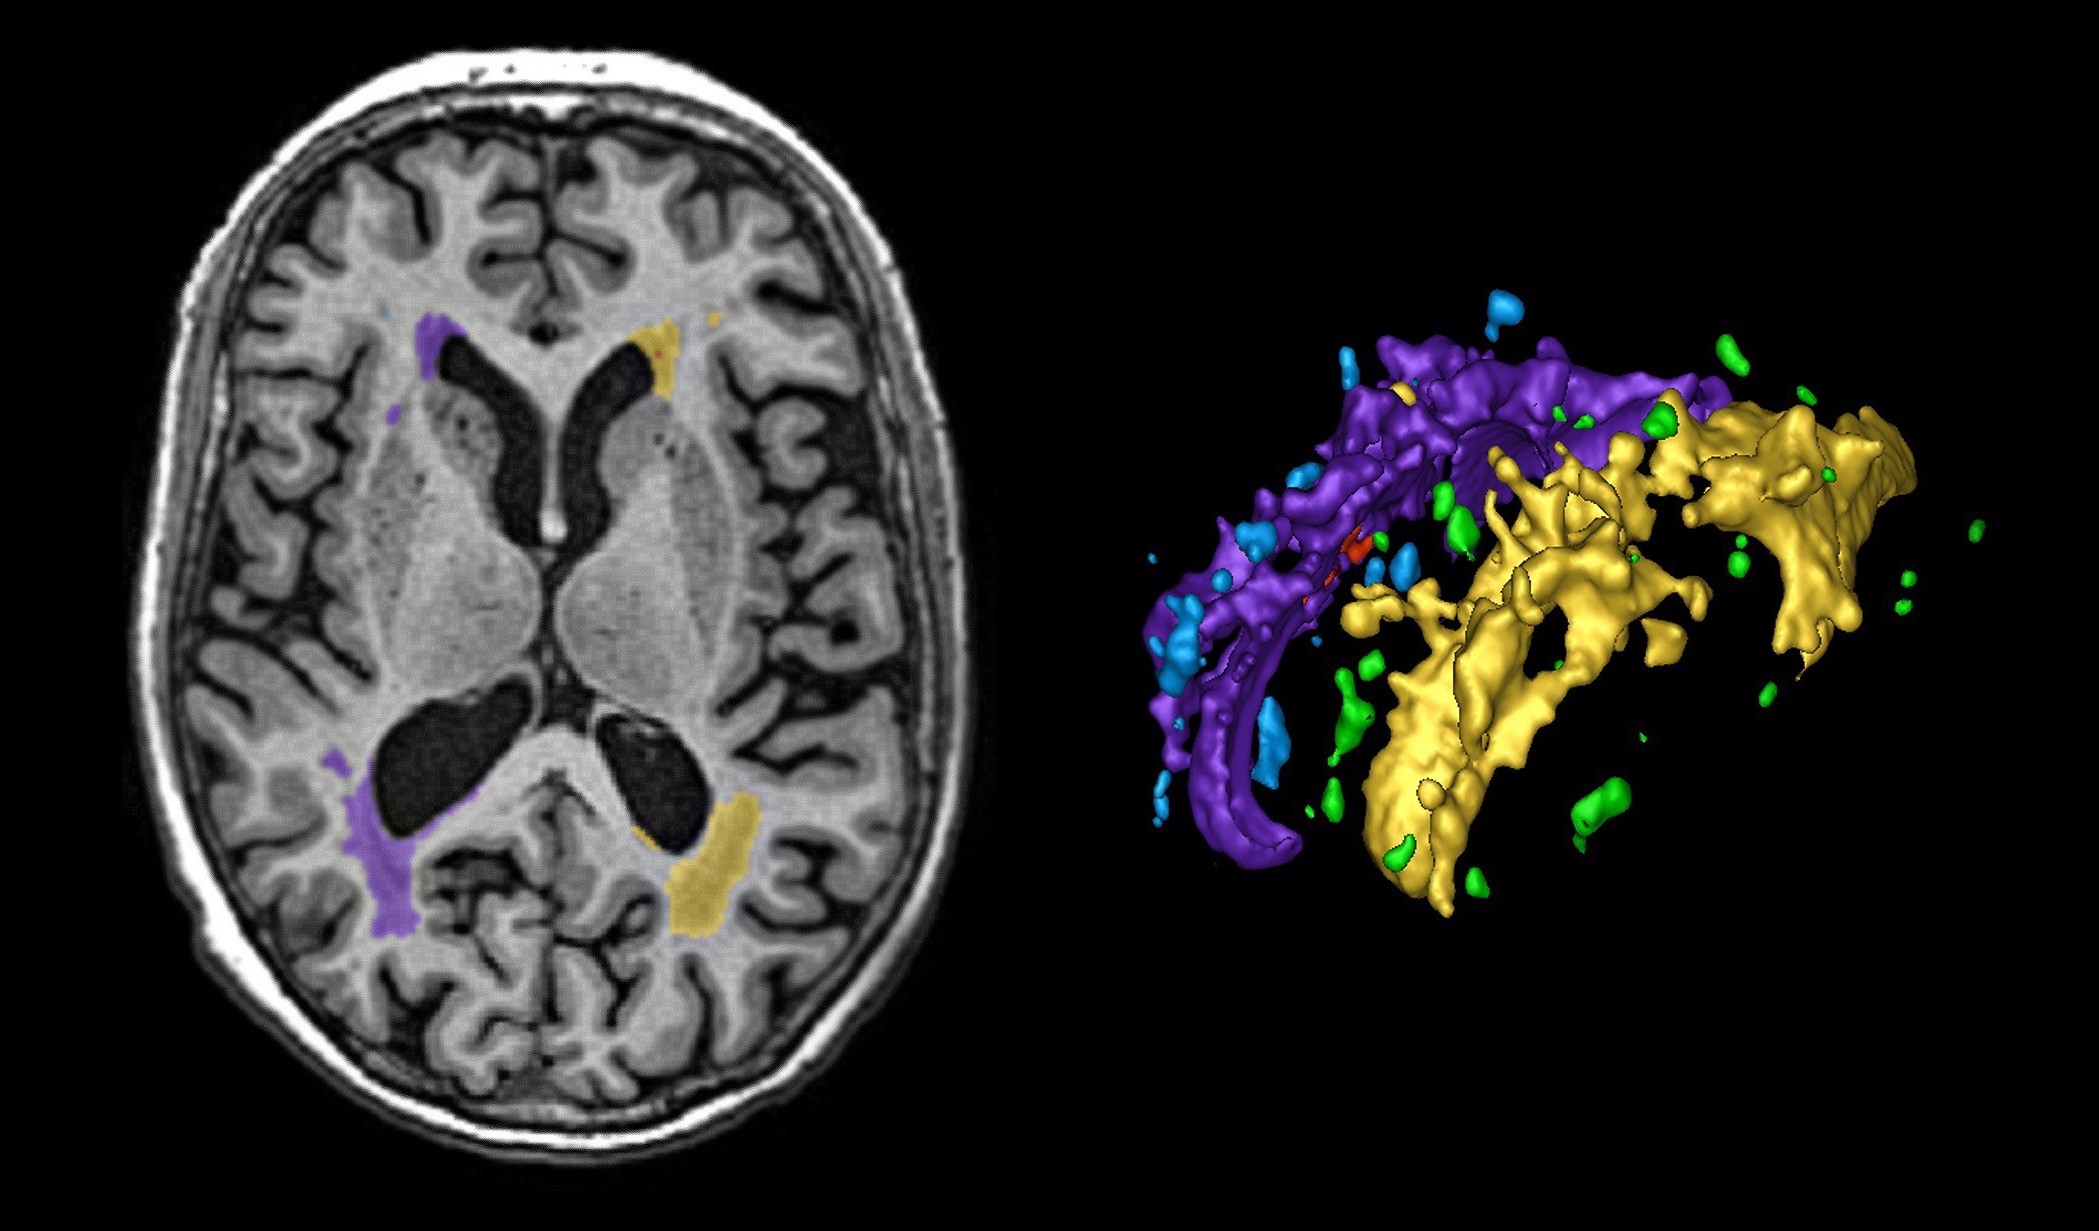

Lesion Explorer: 3D Quantification of White Matter Disease

“About 95% of people over 65 have some degree of this small vessel disease, making it a very prevalent finding in human aging, and 20% of people over 65 have extensive patches in the white matter around the brain’s ventricles.”

Following almost 200 patients to autopsy, Black and her colleagues Drs. Keith and Gao have concluded that these white patches represent excess fluid around veins deep in the brain, whose walls thicken with age and high blood pressure; which makes it challenging for veins to adequately circulate blood and also for toxins, such as amyloid, to be cleared from the brain.